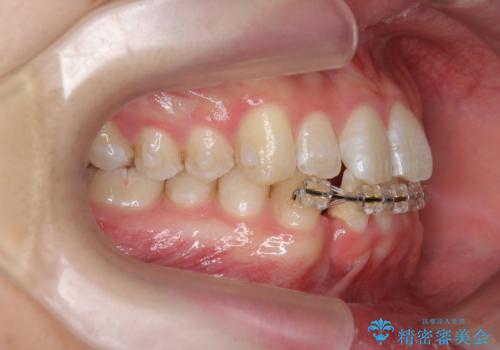

クロスバイト・歯並びが原因の歯肉退縮歯、矯正治療による審美性の改善

- 前歯の歯並び、下顎前歯の歯ぐきの下がり(歯肉退縮)の改善を求めて来院されました。

歯肉退縮の根本的な原因はすれ違った噛み合わせによる為害性のある咬合状態にあるため、歯肉退縮に対し結合組織の移植術を行うのではなく当該歯を抜去し部分矯正を含めた治療計画を立案します。

矯正治療を行ったことで、噛み合わせが安定し審美性も機能性も向上することができました。

- マウスピース型矯正装置の長時間装着(1日20時間以上)が必須です